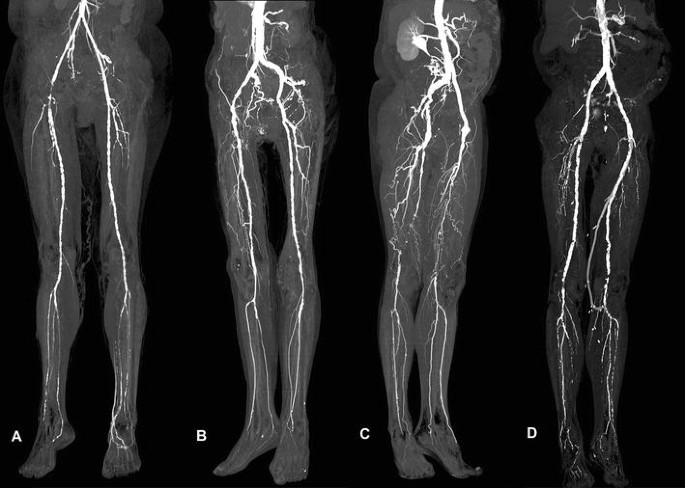

Overview of CT Lower Limb Angiography Scan

CT lower limb angiography is a non-invasive imaging technique that utilizes computed tomography (CT) technology and a contrast dye to visualize the blood vessels in the legs. This detailed imaging allows healthcare professionals to assess the condition of arteries and veins, identifying any blockages, narrowing, or other abnormalities. By providing a comprehensive view of the lower limb's vascular system, CT angiography aids in diagnosing and evaluating conditions such as peripheral artery disease (PAD), blood clots, aneurysms, and vascular malformations. It also assists in planning interventions like angioplasty or surgery, if needed. This safe and efficient procedure offers a valuable tool for diagnosing and managing vascular conditions in the legs, ultimately improving patient outcomes and quality of life.